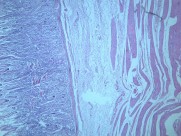

慢性萎缩性胃炎大全(12)张

本病以胃粘膜萎缩变薄,粘膜腺体减少或消失,并伴有肠上皮化生,固有膜内多量淋巴细胞、浆细胞浸润为特点。本性胃炎的病因比较复杂,部分可能与吸烟酗酒和用药不量有关,部分由慢性浅表性胃炎迁移发展而来,还有部分属兔自身免疫疾病。